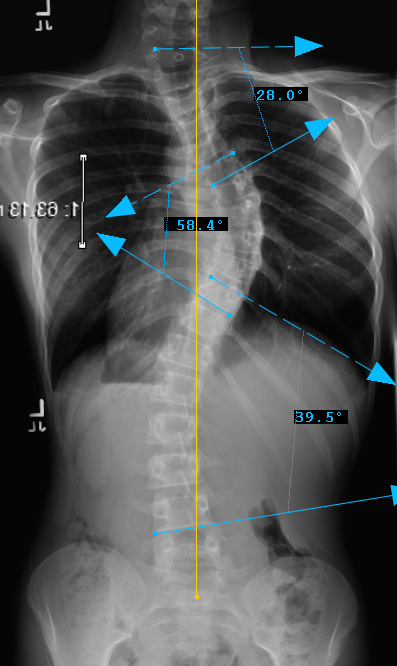

Preop PA View

thoracic curve non-structural, main thoracic curve major, Lumbar curves non-structural.

Curve Type 3

Therefore, Classification is Type 3B-